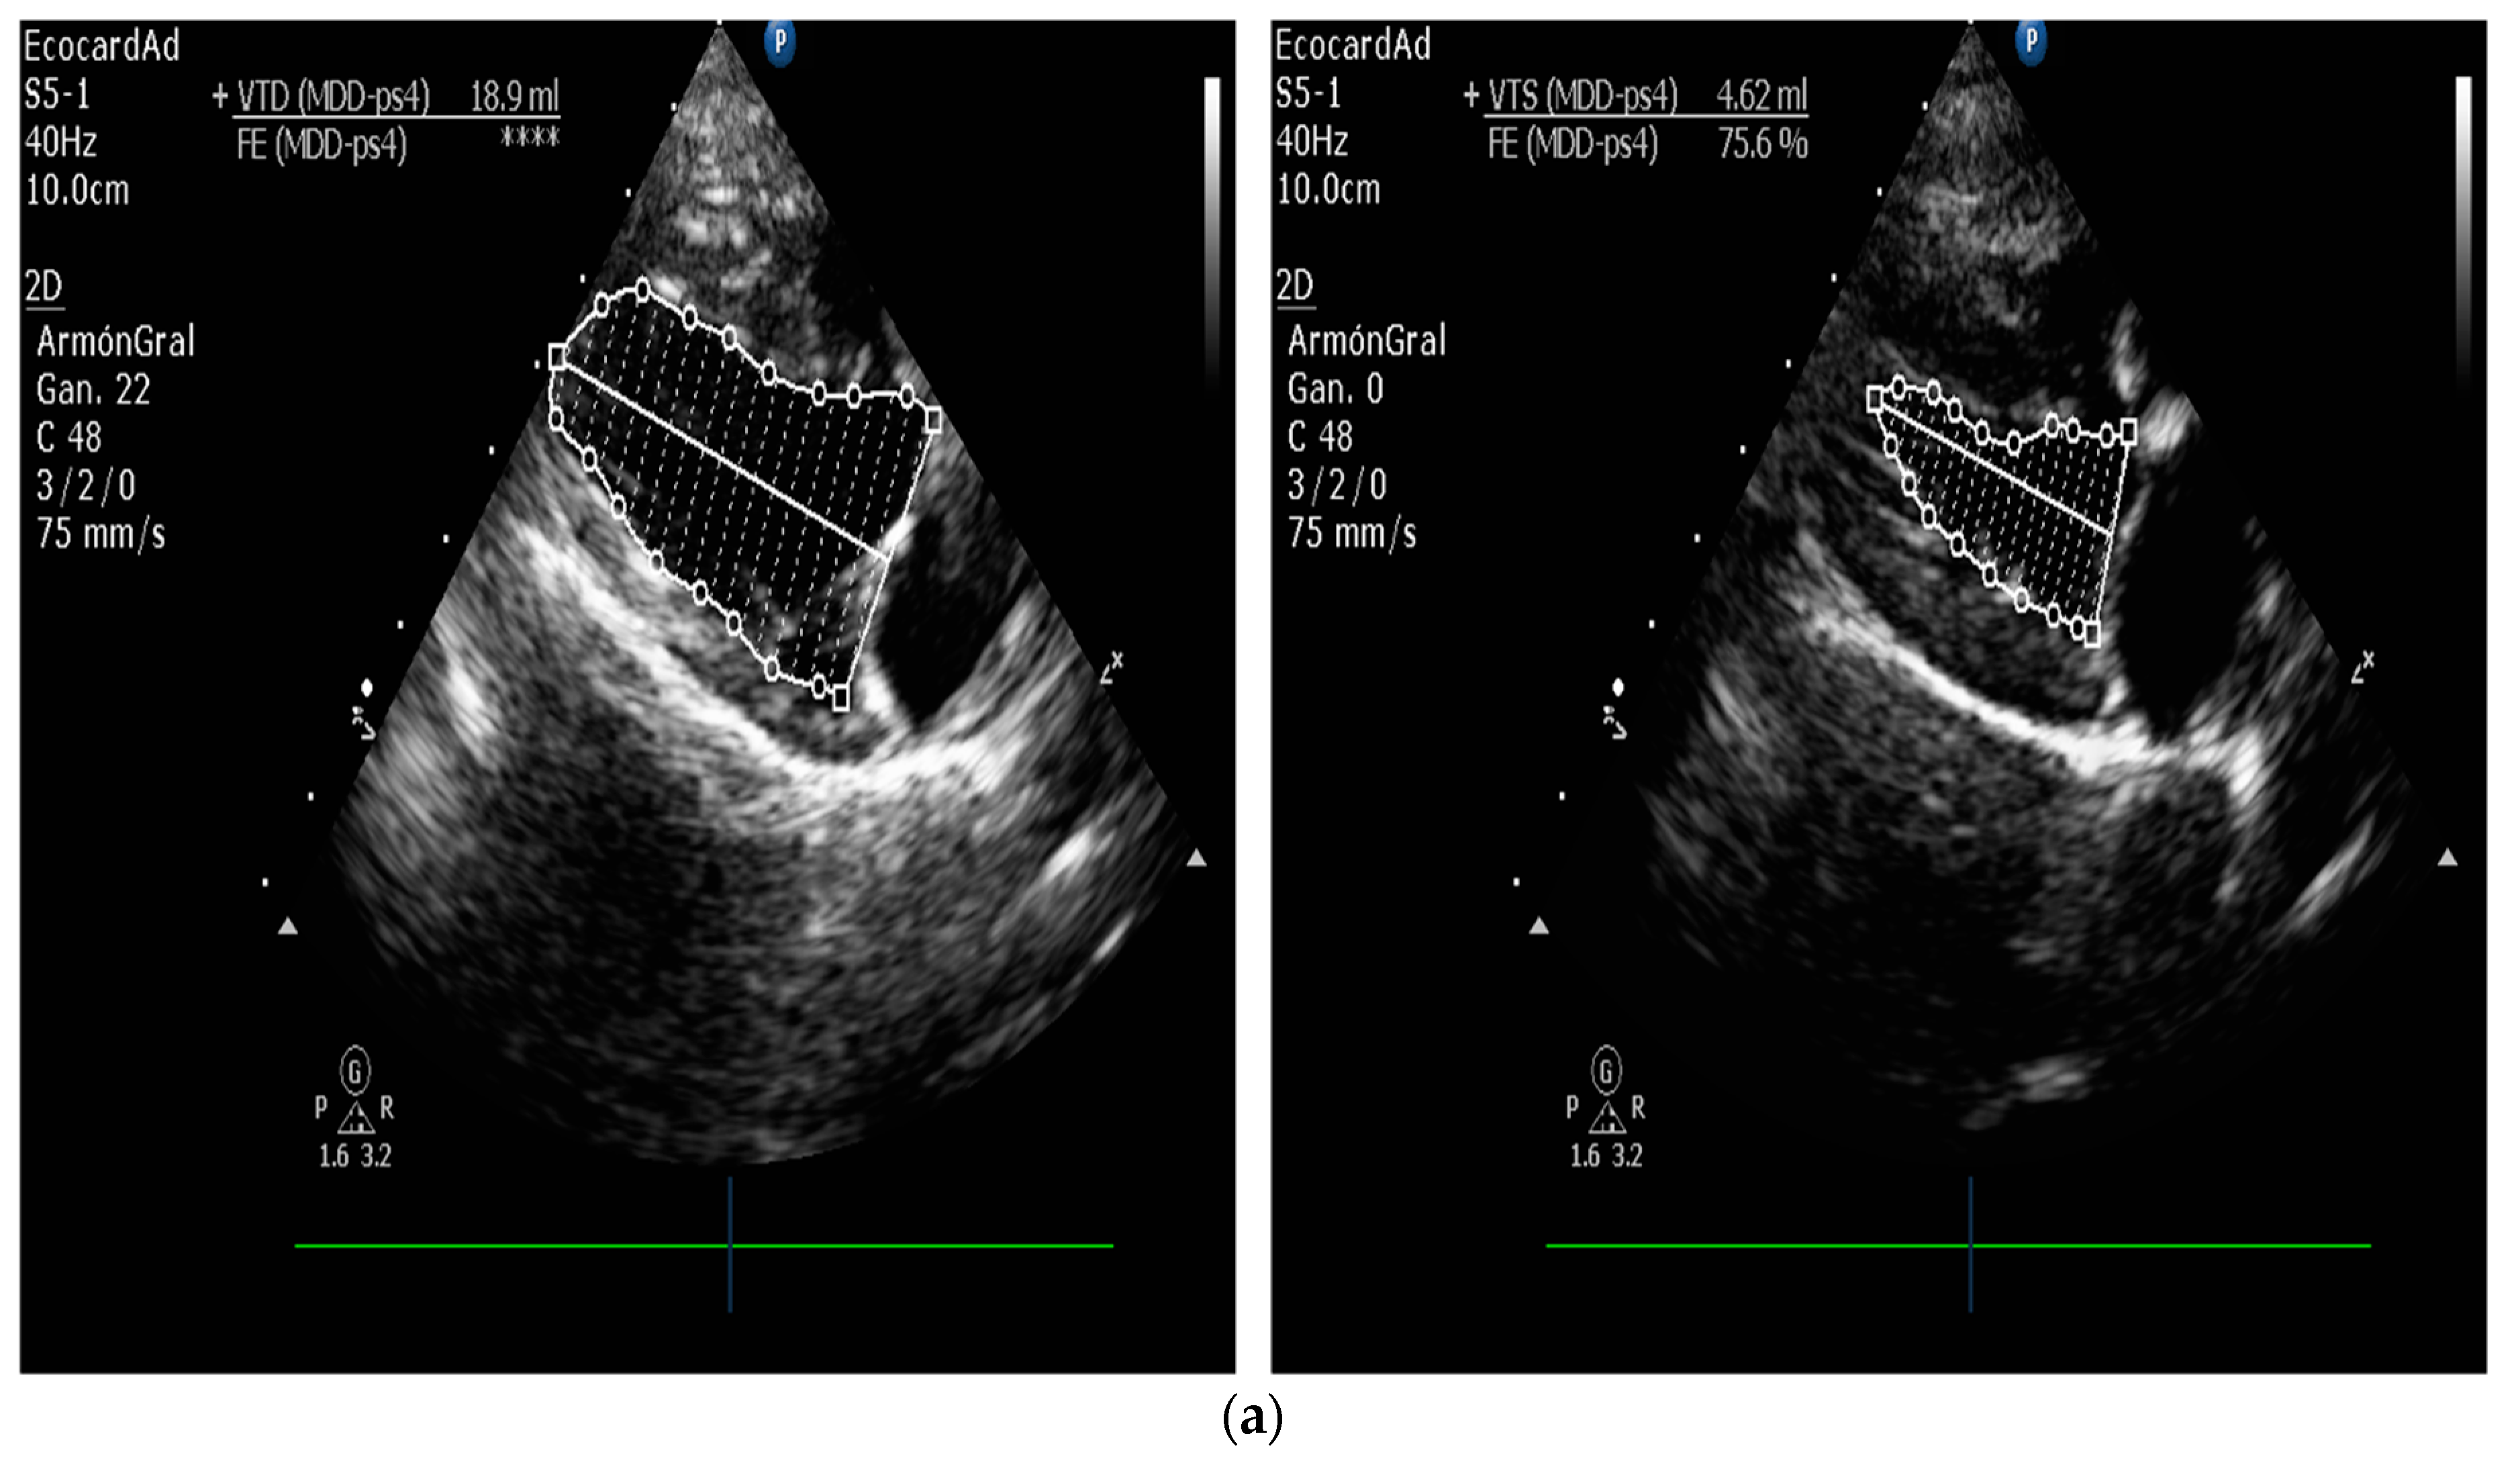

5.1. Echocardiographic Measurements on DCM

5.1.1. Measurement of Left Ventricular Volume by Simpson’s Method of Disks and Left Ventricular M-Mode

- Bonagura, J.D.; Visser, L.C. Echocardiographic assessment of dilated cardiomyopathy in dogs. J. Vet. Cardiol. 2022, 40, 15–50. [Google Scholar] [CrossRef] [PubMed]

- Bellenger, N.G.; Burgess, M.I.; Ray, S.G.; Lahiri, A.; Coats, A.J.; Cleland, J.G.; Pennell, D.J. Comparison of left ventricular ejection fraction and volumes in heart failure by echocardiography, radionuclide ventriculography and cardiovascular magnetic resonance. Are they interchangeable? Eur. Heart J. 2000, 21, 1387–1396. [Google Scholar] [CrossRef] [Green Version]

- Grothues, F.; Smith, G.C.; Moon, J.C.; Bellenger, N.G.; Collins, P.; Klein, H.U.; Pennell, D.J. Comparison of interstudy reproducibility of cardiovascular magnetic resonance with two-dimensional echocardiography in normal subjects and in patients with heart failure or left ventricular hypertrophy. Am. J. Cardiol. 2002, 90, 29–34. [Google Scholar] [CrossRef]

| Measurement of Left Ventricular Volume | M-mode echocardiography is widely used in canine cardiology, but its utility is debated. American Society of Echocardiography recommends against using linear measurements in the human patient. SMOD is recommended [100,102,103]. |